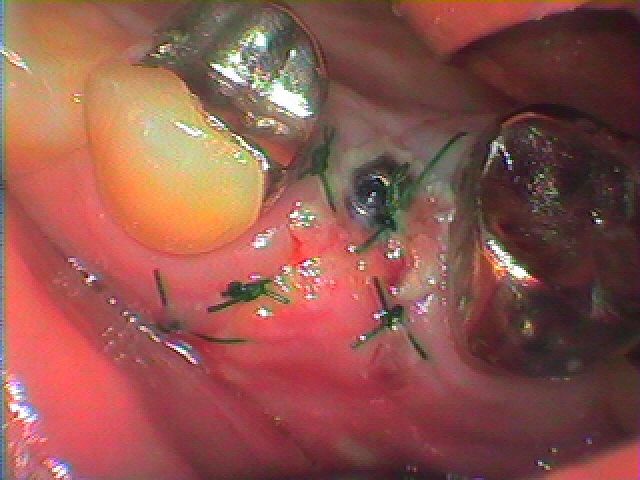

インプラント埋入後の3日目の状態になります

3日目になります